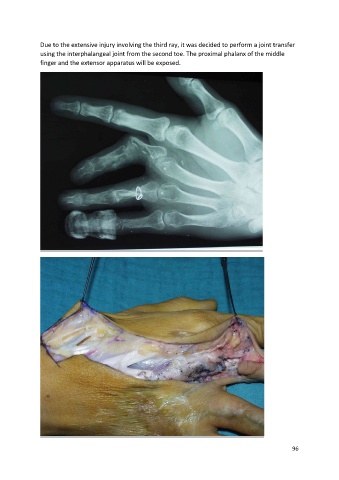

Due to the extensive injury involving the third ray, it was decided to perform a joint transfer

using the interphalangeal joint from the second toe. The proximal phalanx of the middle

finger and the extensor apparatus will be exposed.